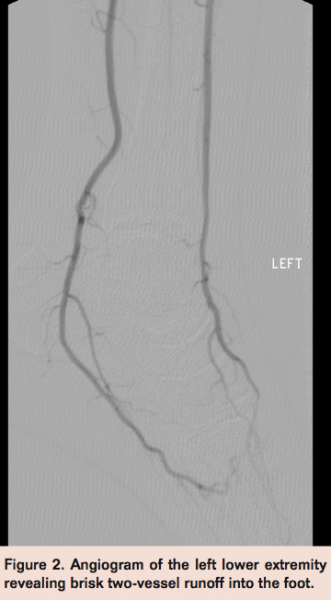

Left lower extremity angiography revealed brisk flow through the femoral and tibial segments with 2-vessel runoff (Figure 2). However, there was noted to be severe stenosis within the plantar arch of the left foot extending from the dorsalis pedis of the anterior tibial artery into the posterior tibial plantar segment (Figure 3).